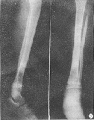

胫腓骨骨折